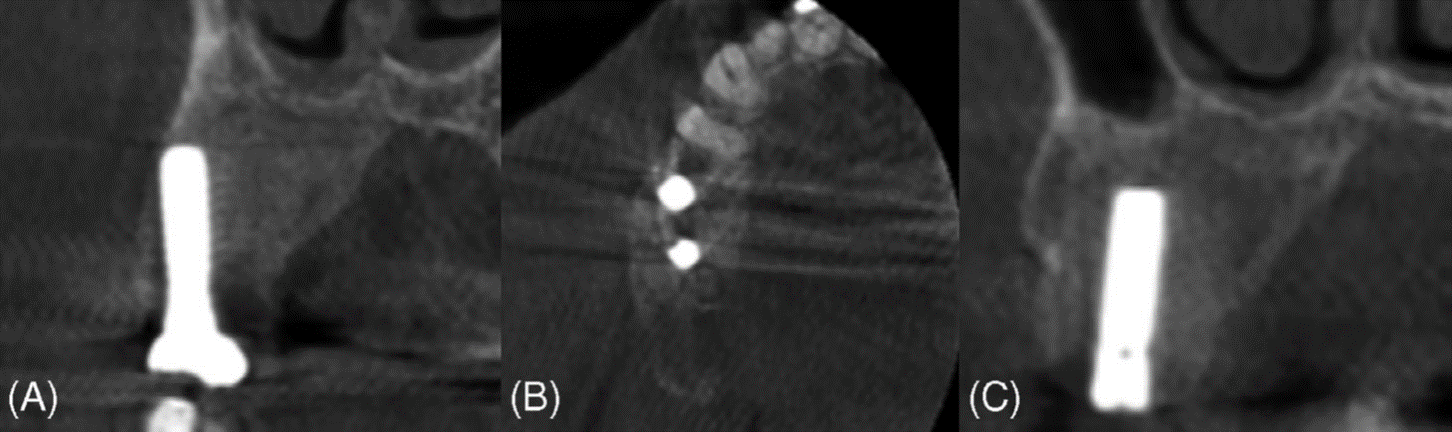

La alteración del contorno del hueso alveolar, la reabsorción o dislocación dental, las relaciones interarcadas anormales y la remodelación de la estructura ósea displásica con el tiempo plantean retos importantes para la rehabilitación oral. Las pruebas sugieren que los implantes dentales pueden tener una alta tasa de supervivencia en pacientes con DF. Una revisión sistemática realizada por Pérez et al. informó de una tasa de supervivencia del 100 % para 36 implantes durante un período de seguimiento medio de 51 meses (4,25 años). Además, un estudio de caso realizado por Monje et al. documentó el éxito de la colocación de un implante en el maxilar izquierdo de un paciente tras Tratamiento DF. Se extrajeron los premolares y el primer molar del paciente y, diez meses después de la extirpación de la lesión, se colocaron implantes. Un periodo de seguimiento de un año mostró una osteointegración satisfactoria, sin signos de inflamación, pérdida ósea ni movilidad. Además, un estudio de caso realizado por Monje et al. documentó el éxito de la colocación de implantes en el maxilar izquierdo de un paciente tras el tratamiento de la DF. Se extrajeron los premolares y el primer molar del paciente y, diez meses después de la extirpación de la lesión, se colocaron los implantes. Un periodo de seguimiento de un año mostró una osteointegración satisfactoria, sin signos de inflamación, pérdida ósea ni movilidad.

La DF representa un subconjunto de diversas displasias óseas que pueden afectar al hueso alveolar, lo que plantea retos únicos en la cirugía oral y maxilofacial. Esta afección altera el proceso normal de remodelación ósea, lo que provoca cambios significativos en la estructura y la estabilidad del hueso. Por consiguiente, es fundamental comprender cómo las displasias óseas como la DF afectan a la osteointegración y a la supervivencia a largo plazo de los implantes dentales. Evaluar los efectos de estas lesiones en el éxito de los implantes es clave para optimizar los resultados de los pacientes y desarrollar estrategias de tratamiento personalizadas. En este caso, un paciente con DF monoestótica en el lado derecho del maxilar superior fue tratado con éxito remodelando toda la lesión y conservando los implantes dentales. Los implantes no mostraron signos de movilidad clínica ni de recurrencia de la enfermedad.